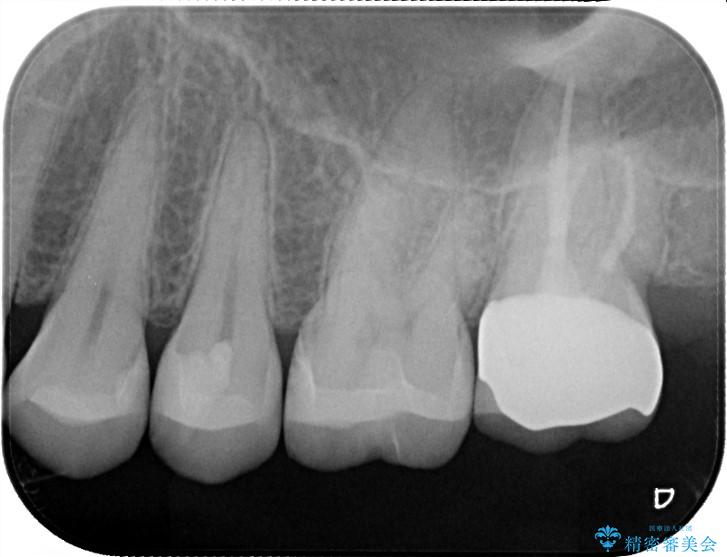

メタルインレーの下と他2歯に虫歯を認めたため治療をすることとしました。

また今後の手入れなどを考慮し、虫歯が再発しにくい素材であるセラミックを選択しました。